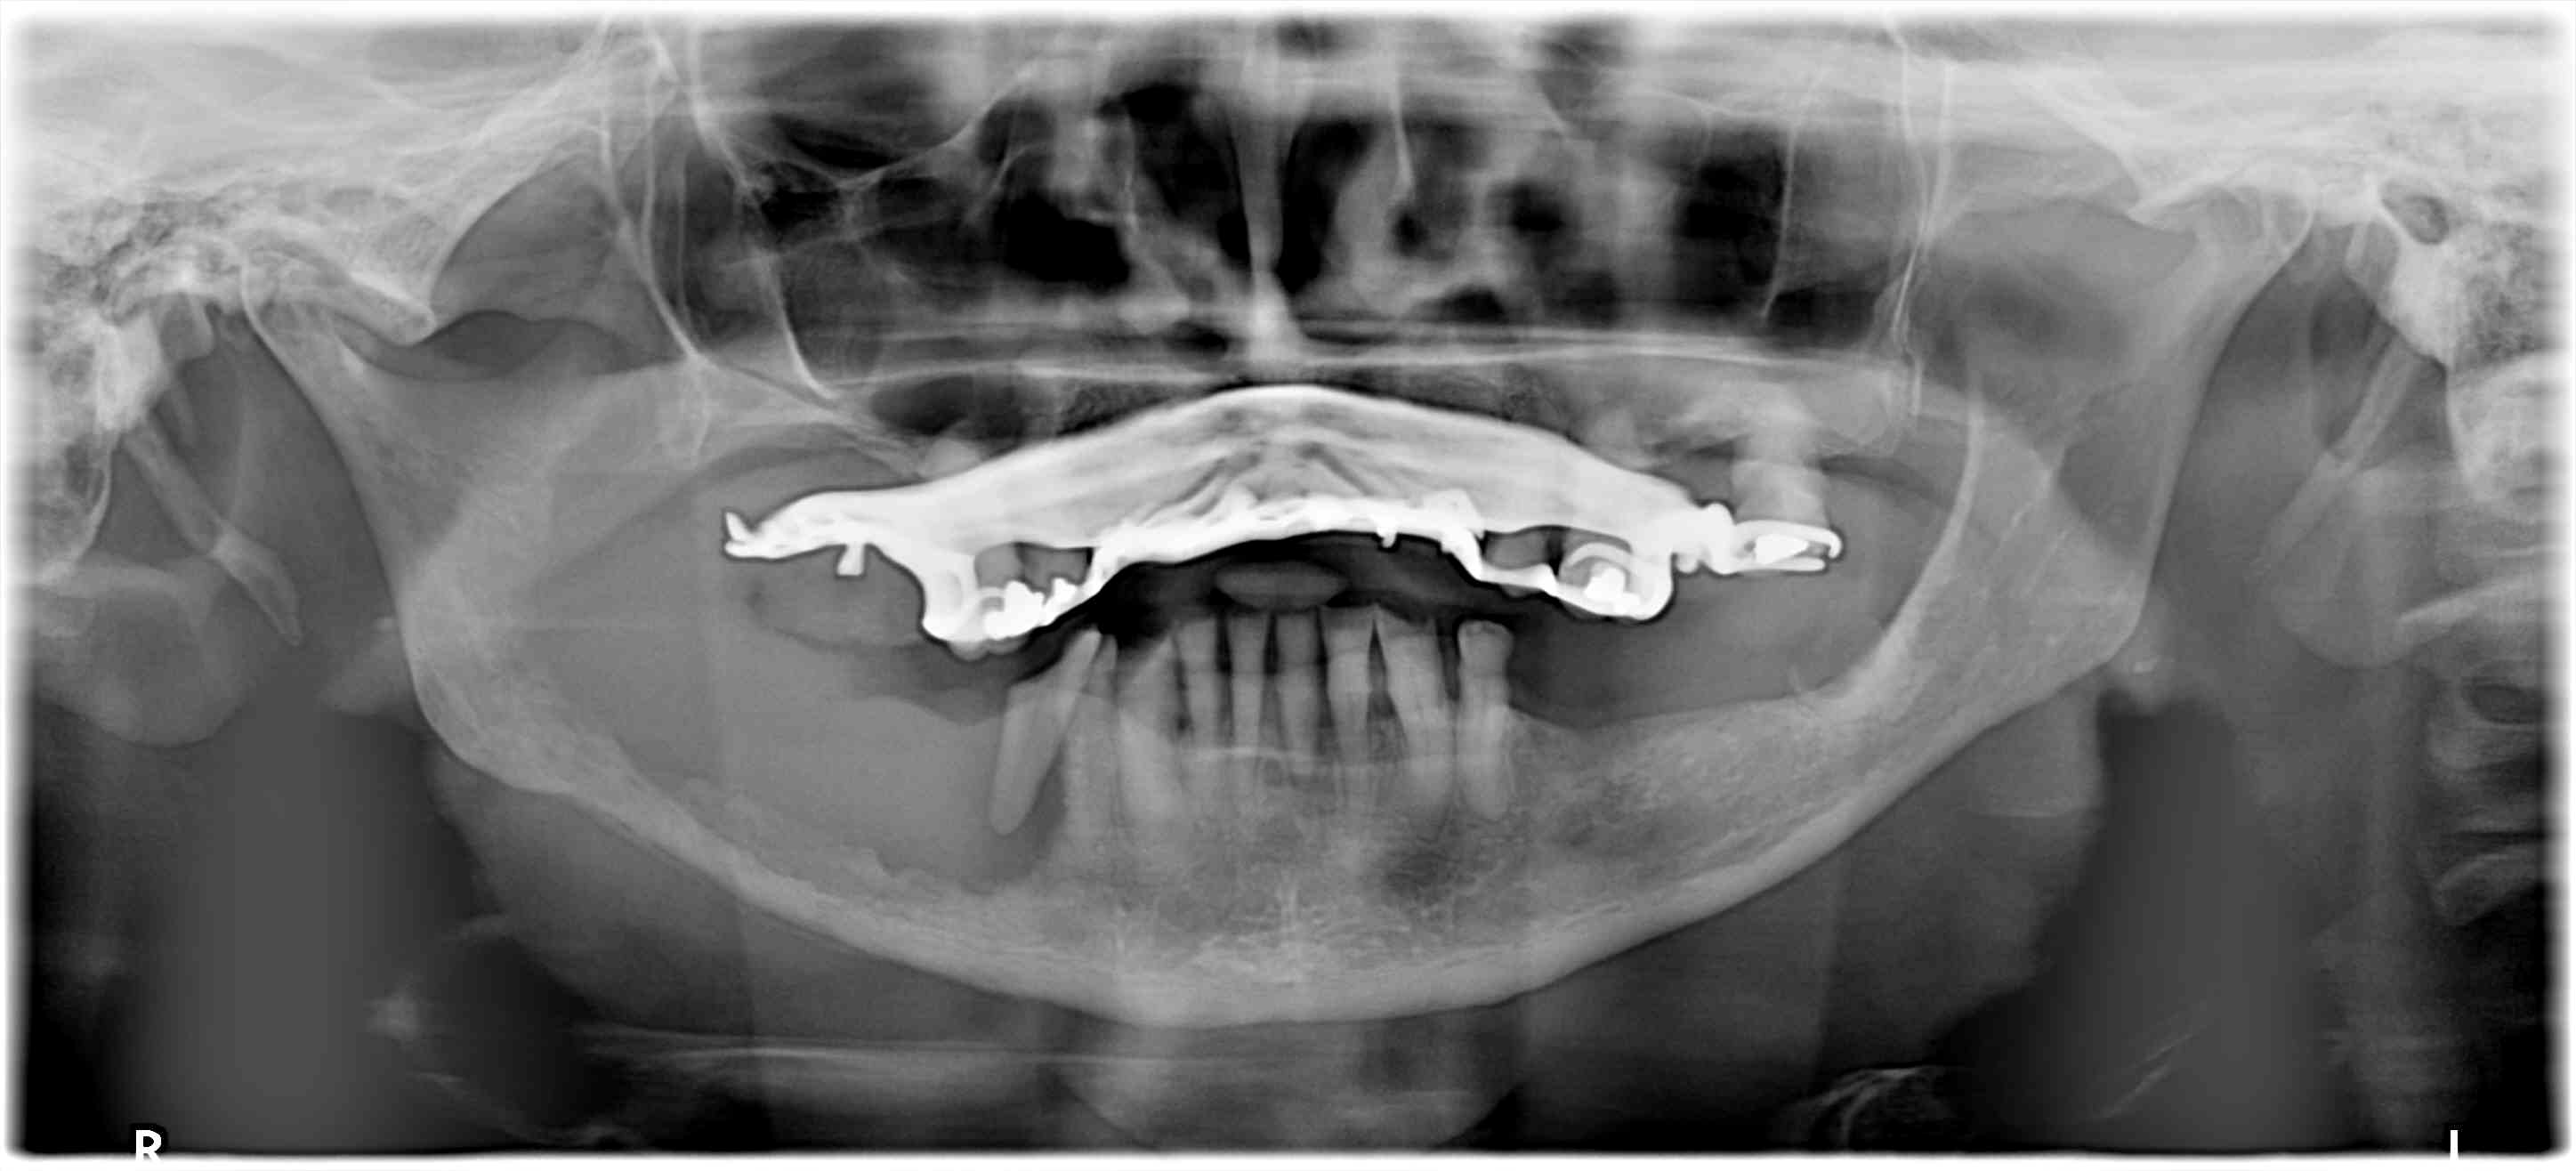

Tiiens par exemple radios recommandées dans ce cas ?

Bilan TIB complet. -)))

Vu vend, suite à une cellulite, ma pano est justifiée, je pense .

2 dents mobiles, en bas à gauche retirées sans radio, par un confrère, semble-t-il avec aucune douleur, mais parce qu'elle elle gênait, il y a 1 mois.